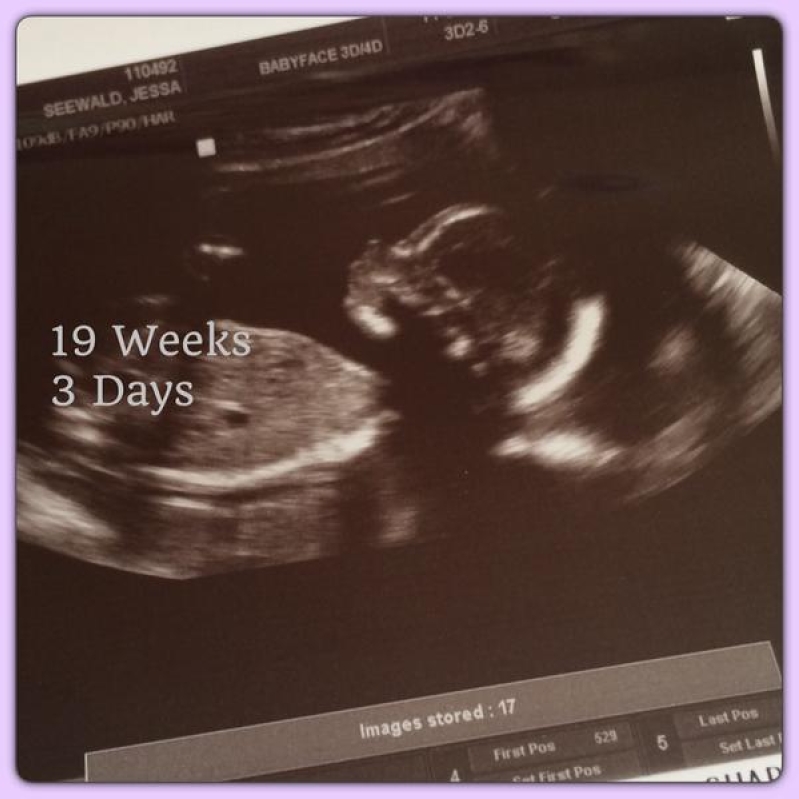

Jessa, wife to 20-year-old Ben Seewald, shared an ultrasound photo of her baby. The picture was captioned, "BabySeewald makes a first appearance today!!! #19weeks3days Yay! Almost halfway! Your daddy and I love you soooo much! #FirstUltrasound --with @ben_seewald"

Jessa explained that she is taking her pregnancy day by day and has welcomed some respite after her morning sickness, due to the pregnancy, is already waning. Jessa is on the 19th week of her pregnancy and is due to give birth on November 1 this year.